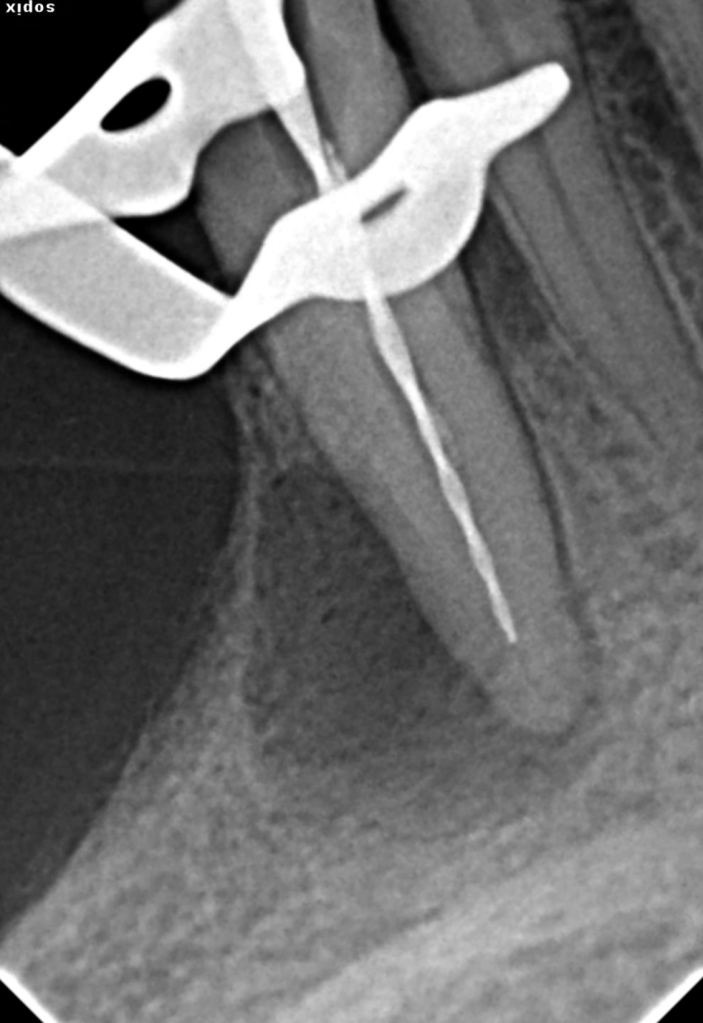

2 Limas rotas + reco Preendo

Lima en conducto MV